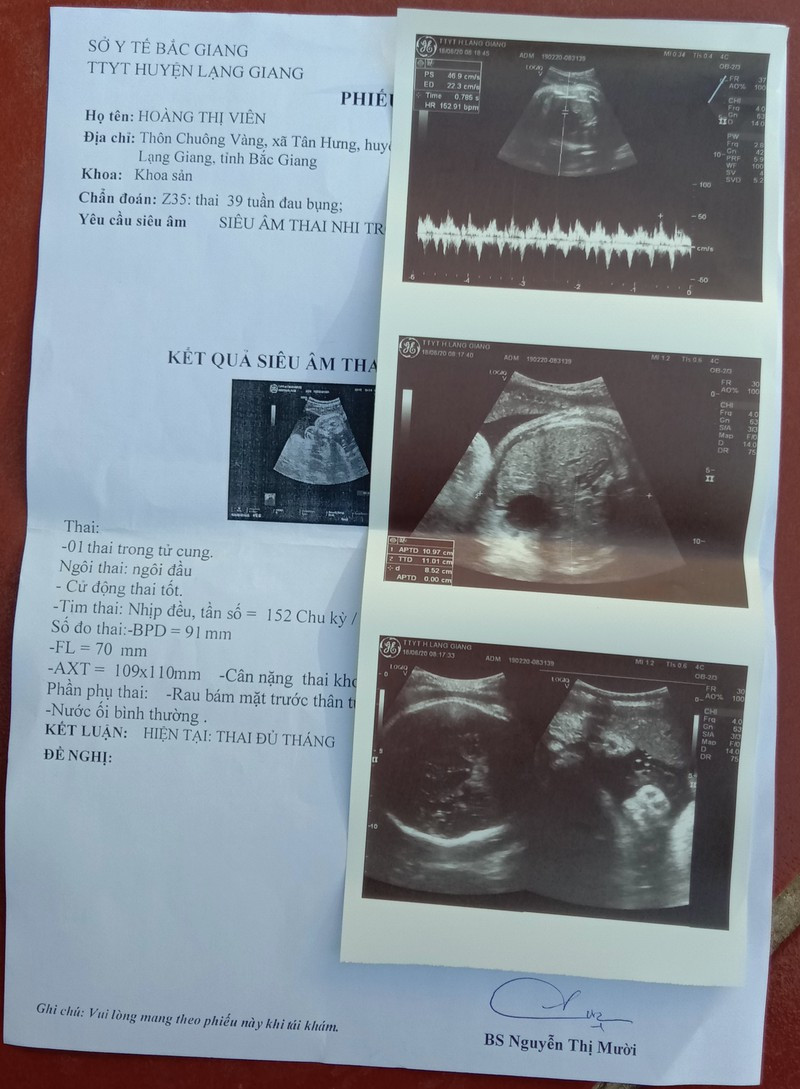

| Kết quả siêu âm của chị H.T.V vài ngày trước đó và không có biểu hiện bất thường. |